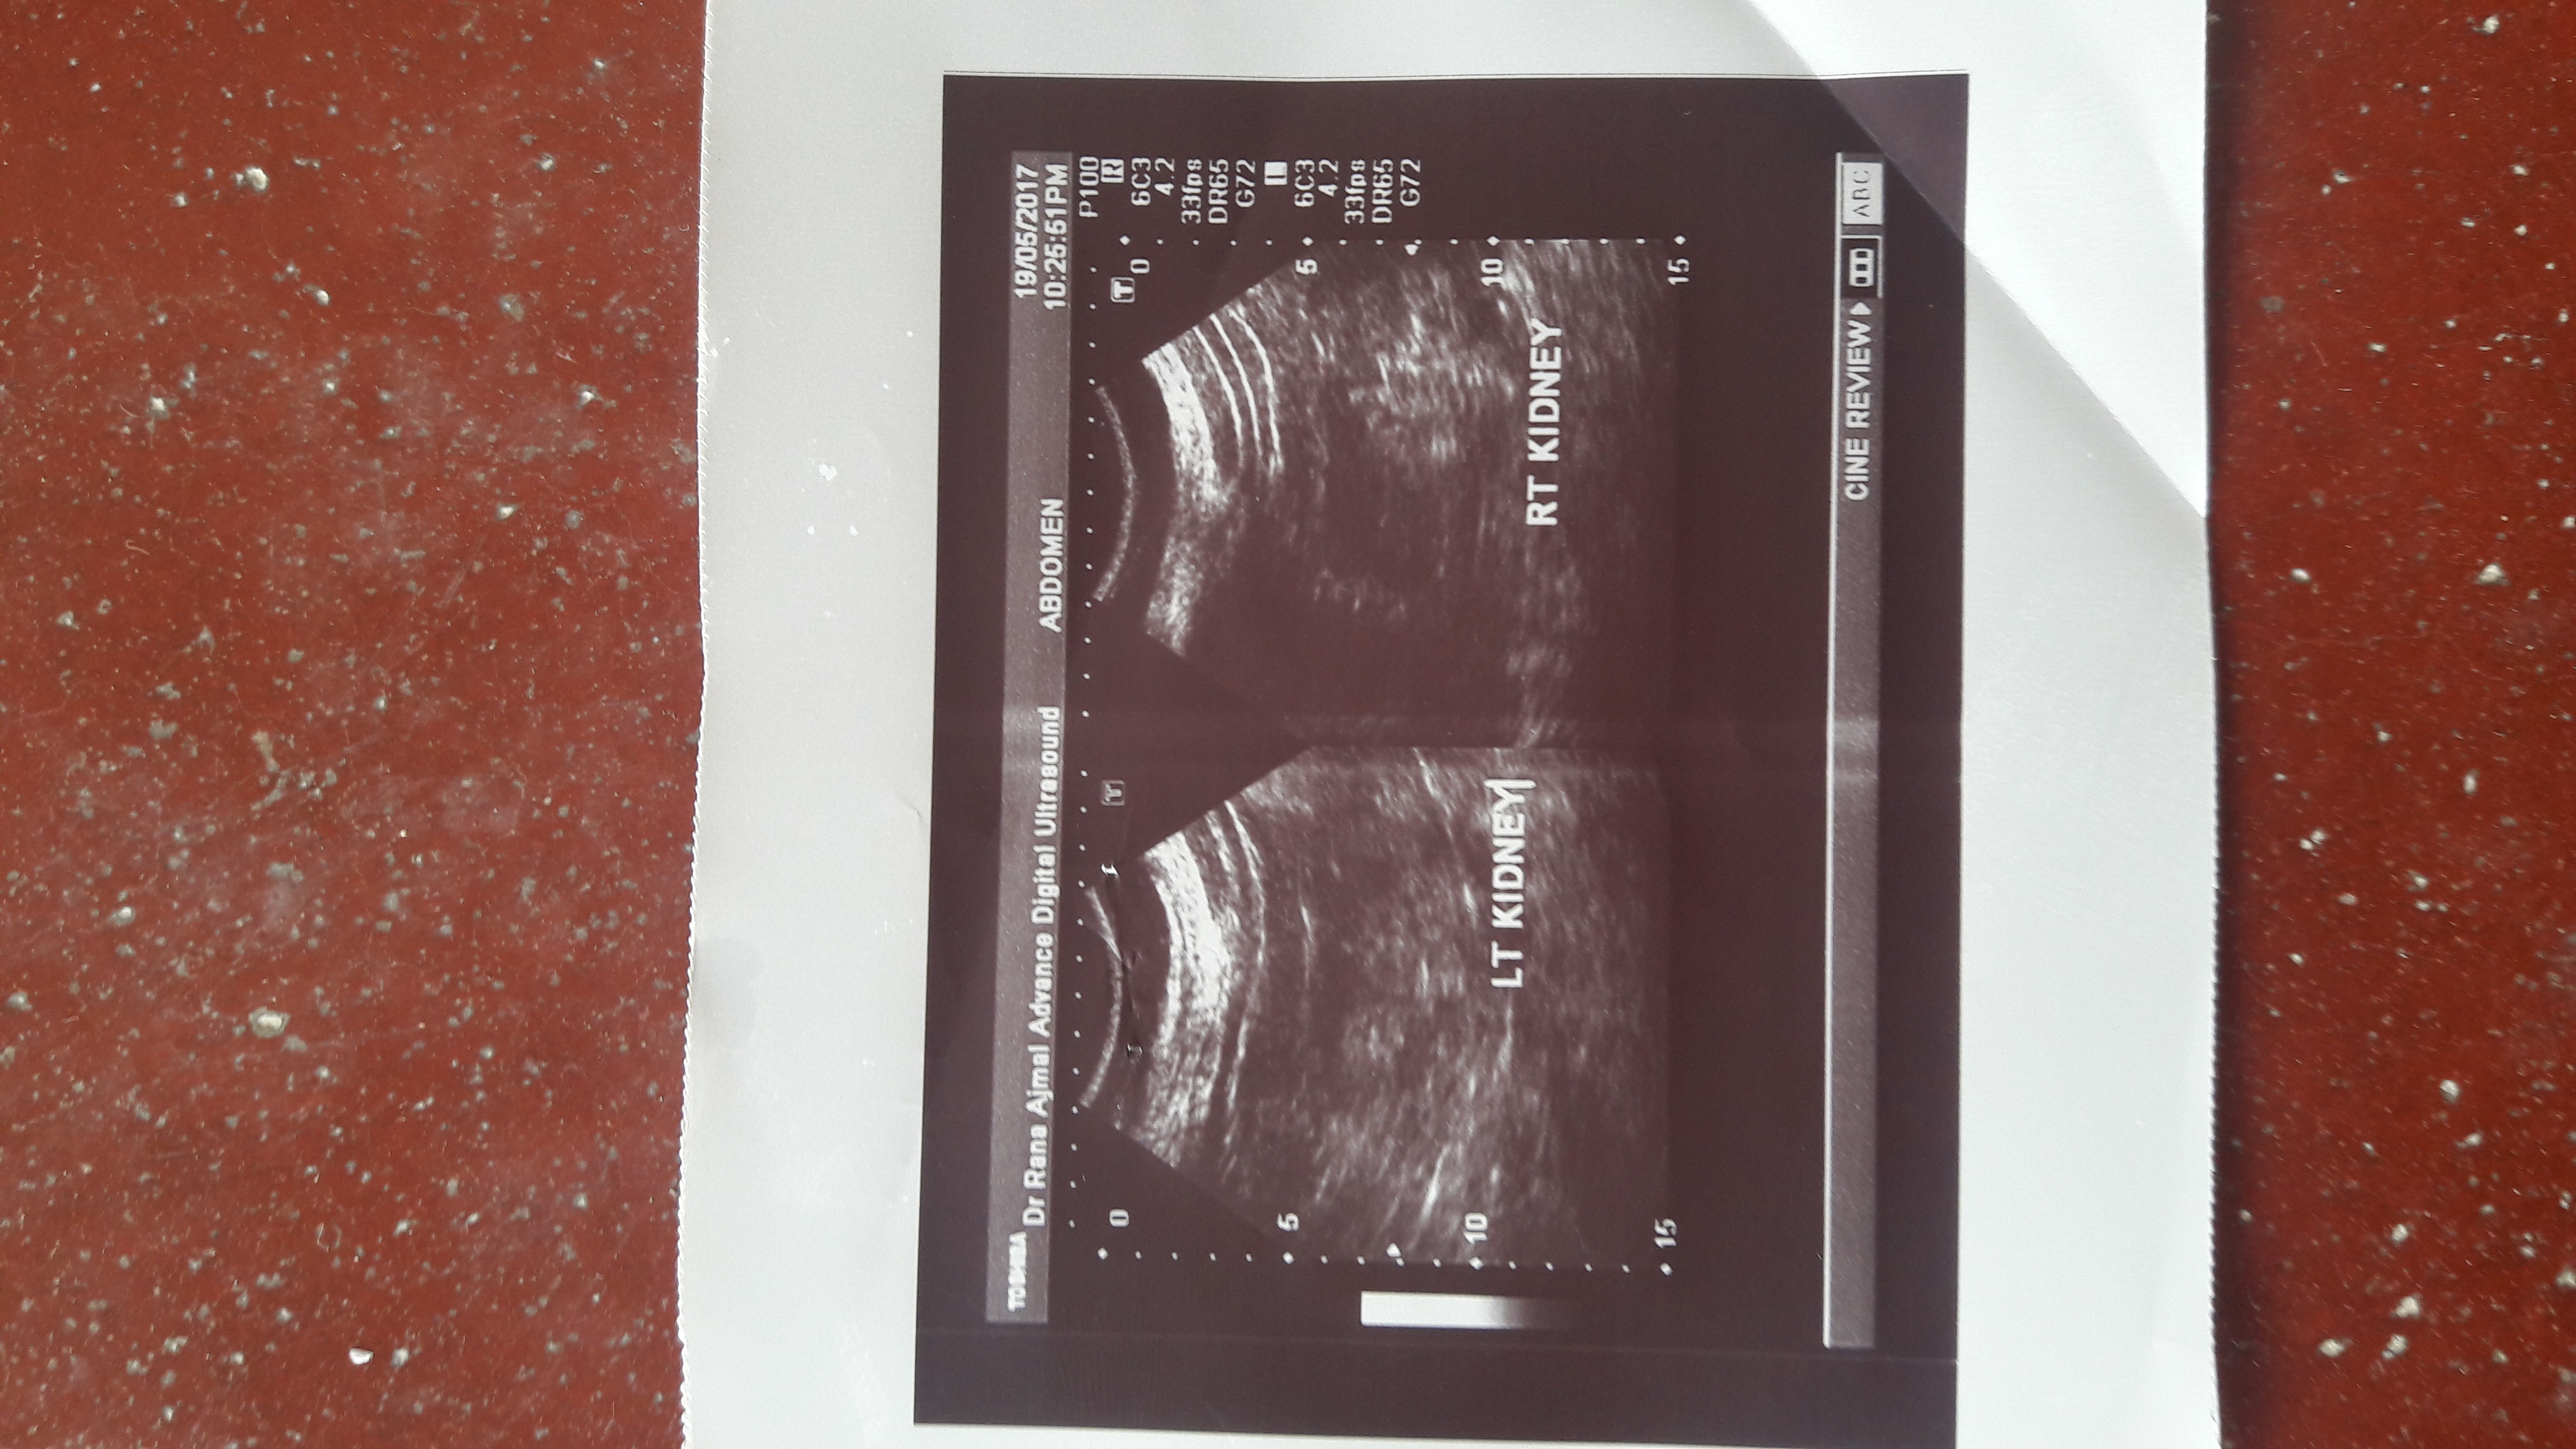

Attach Photo here: